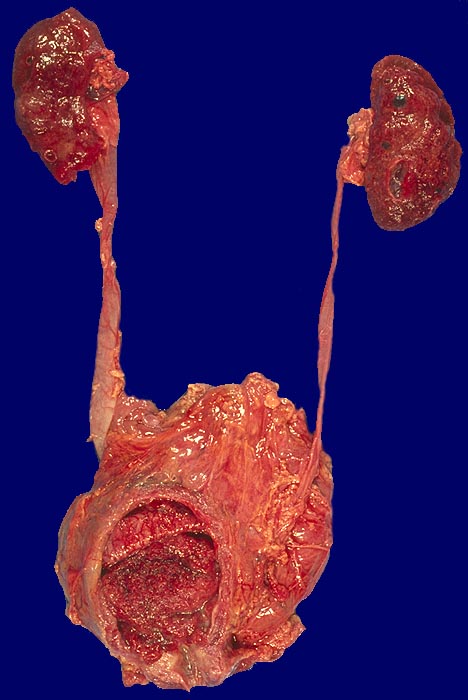

Wenn keine Metastasen vorliegen, kann ein Patient durch radikale operative Eingriffe (Zystektomie mit pelviner Lymphknotendissektion, Nephrektomie) geheilt werden. Bei inoperablen Patienten sollten eine potentiell kurative Bestrahlung oder Chemo-/Radiotherapie erhalten. Bei den primär metastasierten Urothelkarzinomen versprechen Chemotherapien einen guten palliativen Effekt.

Makroskopie

Befund

Pathologischer Befund